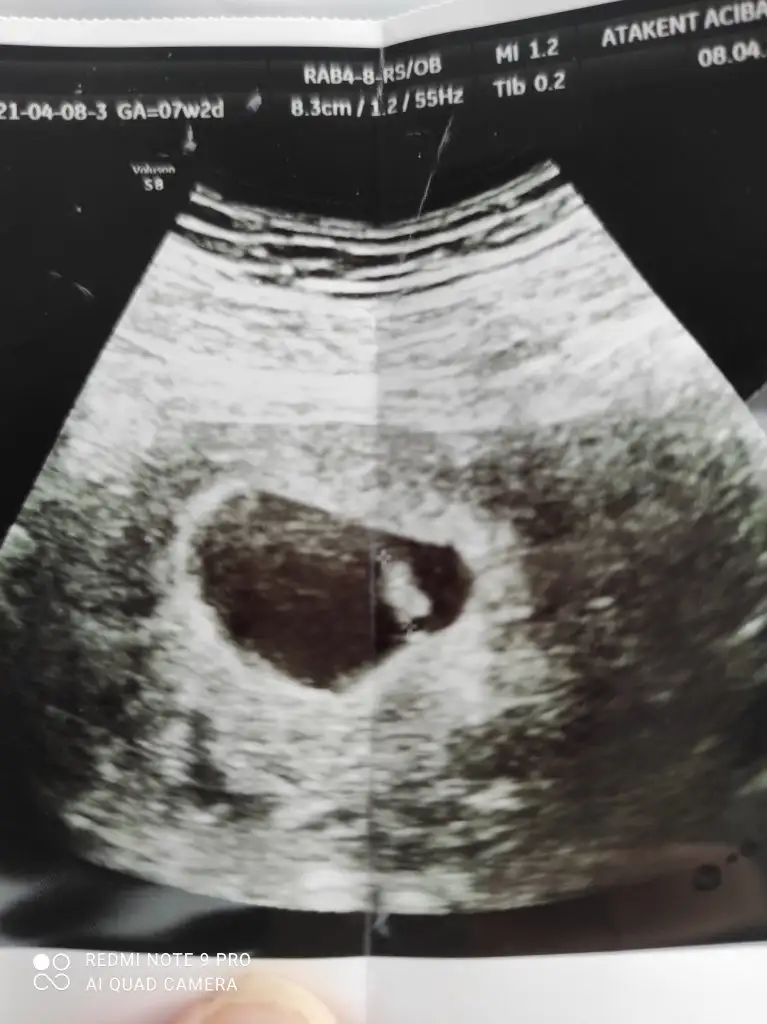

Kız sanki bacak arası boş görünüyorCanım 13+4 ne diyorsun? İlk attığım usg ye kız demiştin ikinciye erkek dedin ama ikisinde de emin değilim daha küçük demiştin. Bende bugün doktora gittin 13+4 haftalıkIkra meyra

12+3 haftalik hamilelik nedir sizce cinsiyyeti ?Erkek ve kız için 11 + 12+ yada 13 hafta usg görüntüsü olmalı açıklamalar asagıda yazıyorrabbim herkesin gönlüne göre nasip etsin inşallah .. ecmain

[/B]Eki Görüntüle 473828 gordugunuz gibi ust taraftaki simgedende anlasildigi gibi eger cikinti paralel ise kiz

yok 30°lik bir aciyla yukari dogru bakiyorsa %99 oglunuz olacak demektir simdi bi kac ornek resimler daha koyacagim kiziminkide dahil

Eki Görüntüle 473831 simdi burada cikintilara bakin eger bel popo cizgisine paralel ise kiz

yok 30 derecelik bir aciyla yukari bakiyorsa erkek